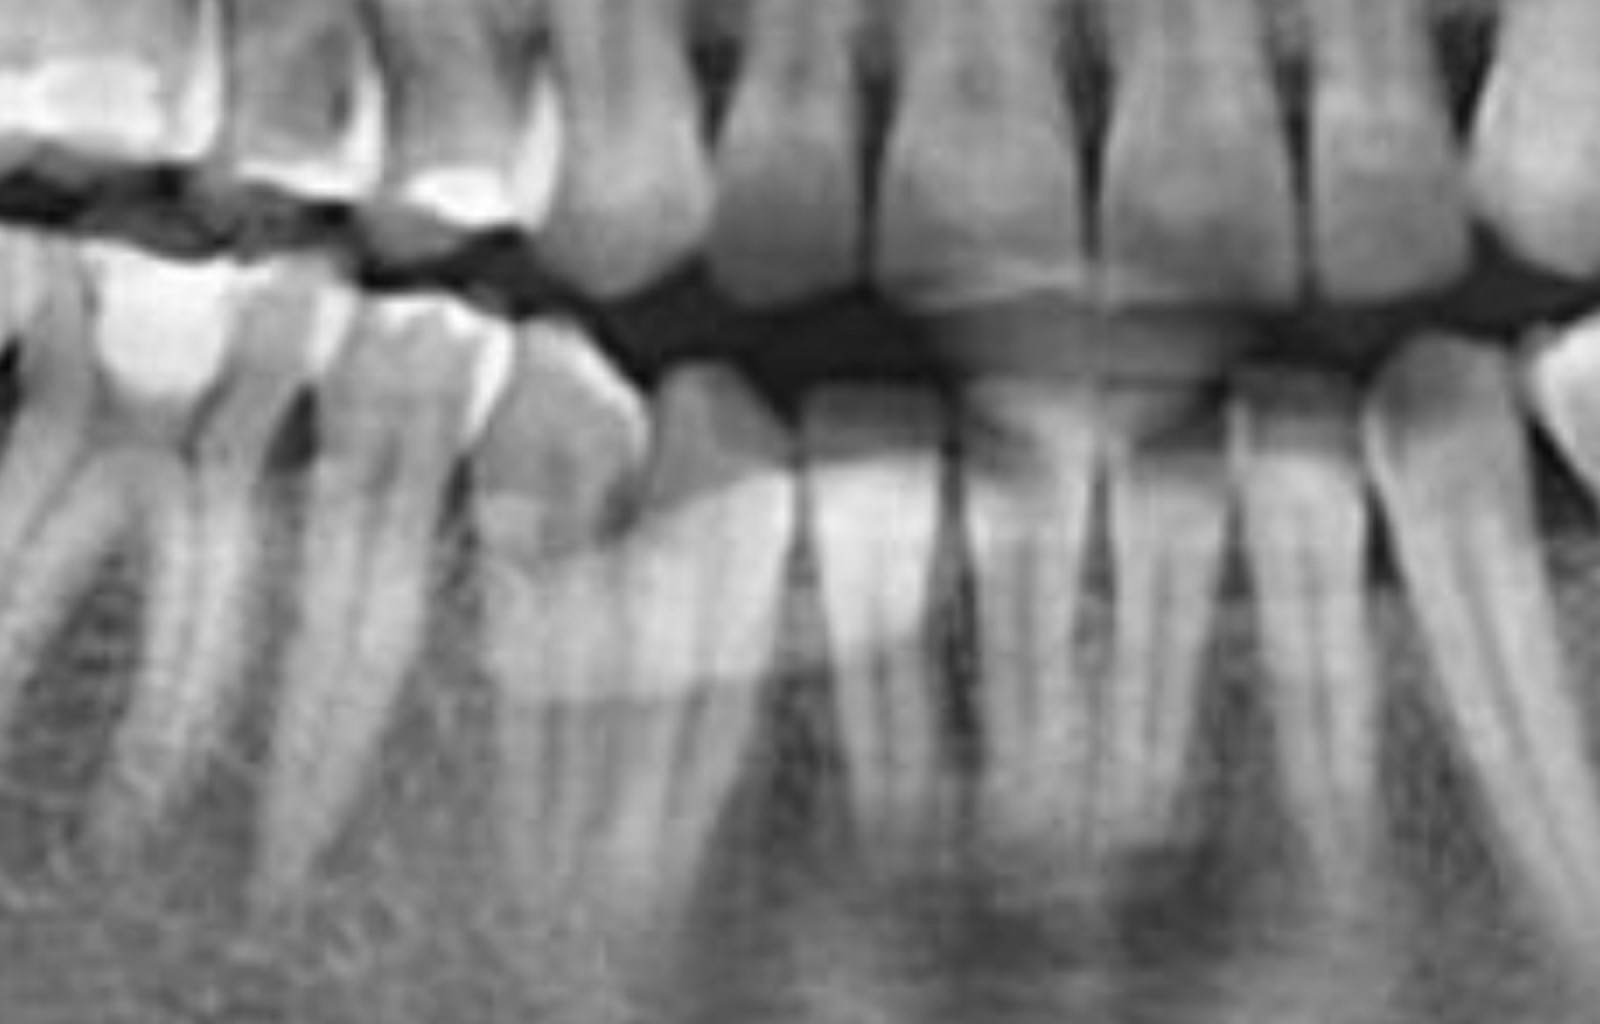

Se presenta paciente femenino de 37 años de edad, con antecedentes patológicos personales y heredofamiliares negados, su motivo de consulta "inflamación en piso de boca". La paciente refiere aumento de volumen en piso de boca de lado derecho de cinco días de evolución, asimismo ardor y dolor al comer. Acude al médico general el cual prescribe antibiótico y analgésicos con un presunto diagnóstico de absceso, la paciente no presentó mejoría asociada a dicha terapéutica médica. A la exploración clínica extraoral, durante la inspección se aprecia una asimetría asociada a un aumento de volumen en la región submandibular (triángulo digástrico), a la palpación se percibe dicho aumento indurado y la paciente refiere dolor. De forma intraoral se aprecia un aumento de volumen de 3 cm en el piso de boca, asociado al conducto de Wharton del lado derecho, con una mucosa inflamada, eritematosa, con un punto blanco compatible con una fístula. A la palpación se encuentra indurado y con dolor (Figura 2). En la maniobra de digitopresión para ordeñar la glándula submandibular, se pudo apreciar salida de escaso material purulento el cual drenaba a través de la fístula, sin permeabilidad ni drenaje de la carúncula. La radiografía panorámica demostró un área radiopaca de forma ovalada en el piso de la boca, cerca de los cuellos de los premolares y en la región de los dientes anteriores inferiores. Se solicitó una tomografía computarizada para una mejor delimitación de la lesión, la cual reveló un cuerpo hiperdenso de alrededor de 30 mm en la región submandibular derecha (Figura 3). Los hallazgos clínicos e imagenológicos llevaron al diagnóstico de sialolito asociado al conducto submandibular. Debido al tamaño y la localización del cálculo, se optó por la extirpación quirúrgica del sialolito de manera ambulatoria con la preservación de la glándula submandibular.

Figura 3